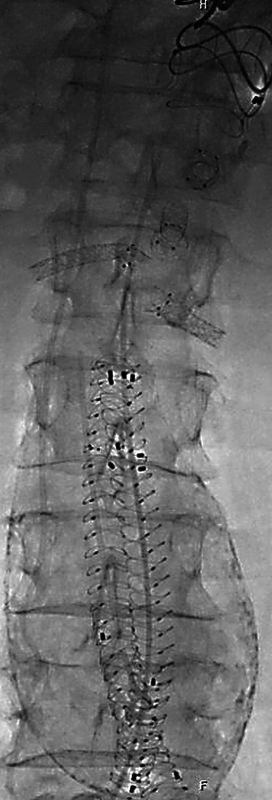

Case description: An 82-year-old male was diagnosed with polyaneurysmal disease. He was treated by femoral, popliteal, and profundal interposition grafts as well as fenestrated endovascular repair (FEVAR) using an Anaconda (Terumo Aortic, Inchinnan, Scotland) endoprosthesis combined with BeGraft peripheral and BeFlared (BF) bridging stent grafts (Bentley InnoMed, Hechingen, Germany).

Conclusion: Polyaneurysmal disease in an aged patient can be treated successfully by thorough case planning, staging of procedures, and combining different vascular surgical techniques. It demonstrates the smooth implantation of the BeFlared in an Anaconda FEVAR.